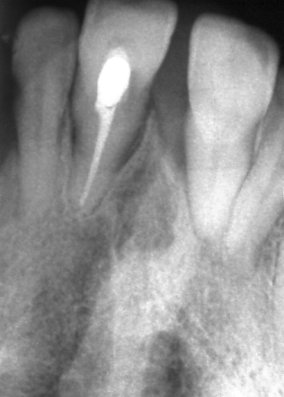

Добре пролекувани зъби

Ендодонтия